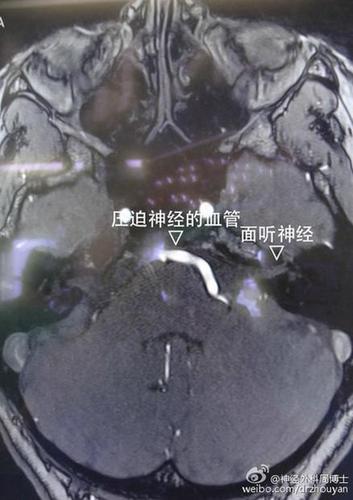

这是一例左侧面肌痉挛的病人,术前的脑MRI提示左侧面神经根部有明显的血管压迫。(这个是在德国学习时完成的病例)